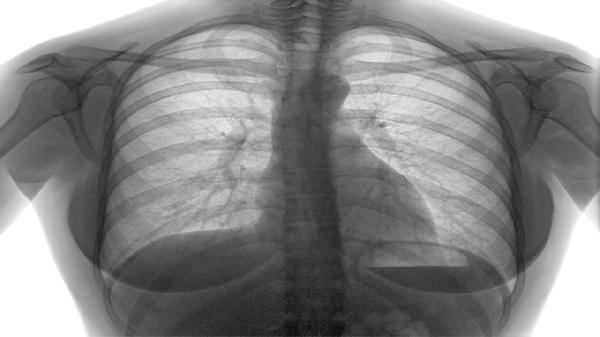

慢阻肺会引起心脏病吗 慢阻肺会引起哪些并发症

慢阻肺可能引起心脏病,常见并发症主要有慢性肺源性心脏病、呼吸衰竭、自发性气胸、骨质疏松、焦虑抑郁等。慢阻肺即慢性阻塞性肺疾病,是以持续气流受限为特征的疾病,长期缺氧和炎症反应可导致多系统损害。